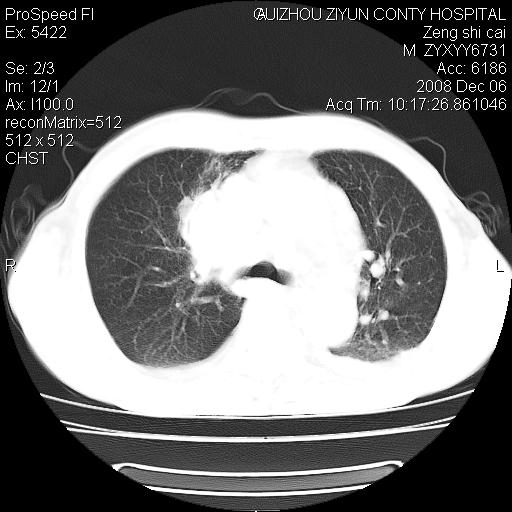

标题: CT16961:M、71岁,咳嗽半年,无血痰;胸片示右肺占位。 [打印本页]

标题: CT16961:M、71岁,咳嗽半年,无血痰;胸片示右肺占位。

右肺纵隔型肺癌伴纵隔淋巴结转移!双侧胸水!

1)考虑右肺上叶纵隔型肺癌伴纵隔淋巴结转移。2)心包积液,双侧胸腔积液。

右肺癌并纵隔淋巴结及胸膜心包转移,好多团团点点,看得有点想吐

右肺上叶纵隔型肺癌伴纵隔淋巴结转移。心包积液,双侧胸腔积液。

建议强化!主要鉴别是淋巴瘤与肺癌淋巴结转移。